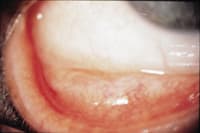

An excellent test for diagnosing allergies, especially allergic conjunctivitis is the Mag test or Mag sign. Nicholas Maganias first reported this test in 1981. A clinician performs the test by pulling down the lower eyelid while the patient looks upward. The test is positive if the examiner notices a half moon or crescent bulging out, demonstrating proptosis of the lower eyelid. The Mag sign is pathognomonic of significant allergic conjunctivitis (Figure 4).

Figure 4. The Mag sign indicates significant allergic conjunctivitis. | |